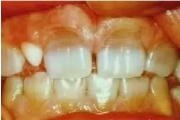

Normaalse jäävhammaskonna pilt küljelt ja eest vaadatuna.

Fluoroos

Fluoroosi

Hammaste defektid

Emaili hüpoplaasiad